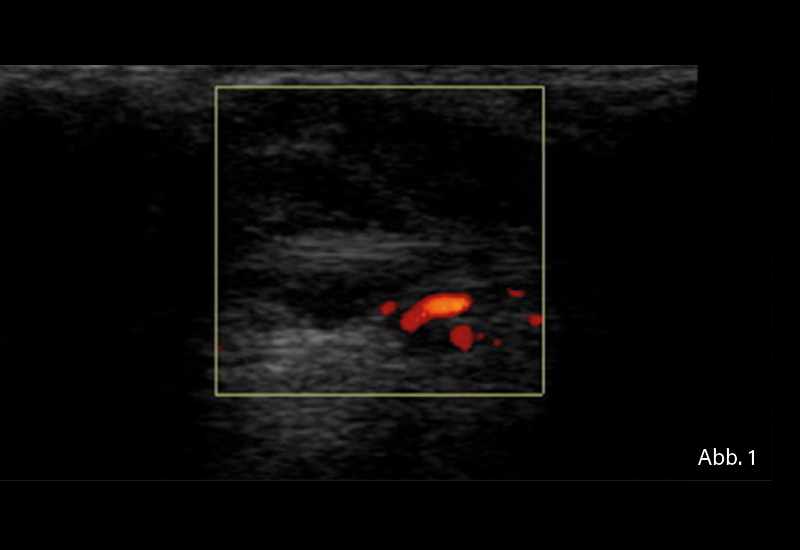

BILDGEBENDE DIAGNOSTIK: Gelenksonografie

DIAGNOSE: Tenosynovitis der Sehne des Musculus extensor carpi ulnaris

bei seropositiver RA

Der sonografische Nachweis einer Tenosynovitis der Sehne des Musculus extensor carpi ulnaris (ECU) spielt eine entscheidende Rolle in der Frühdiagnostik der RA. Die frühzeitige Erkennung entzündlicher Veränderungen ermöglicht eine zeitnahe therapeutische Intervention, die den Krankheitsverlauf positiv beeinflussen kann. Die RA manifestiert sich häufig zunächst an den Händen und Handgelenken. Dabei ist die Tenosynovitis der ECU-Sehne ein häufiger Befund. In einer Studie wurde Tenosynovitis bei mindestens einem anatomischen Ort bei 48,8 % der RA-Patienten festgestellt, wobei die ECU-Sehne zu den am häufigsten betroffenen Sehnen gehörte.